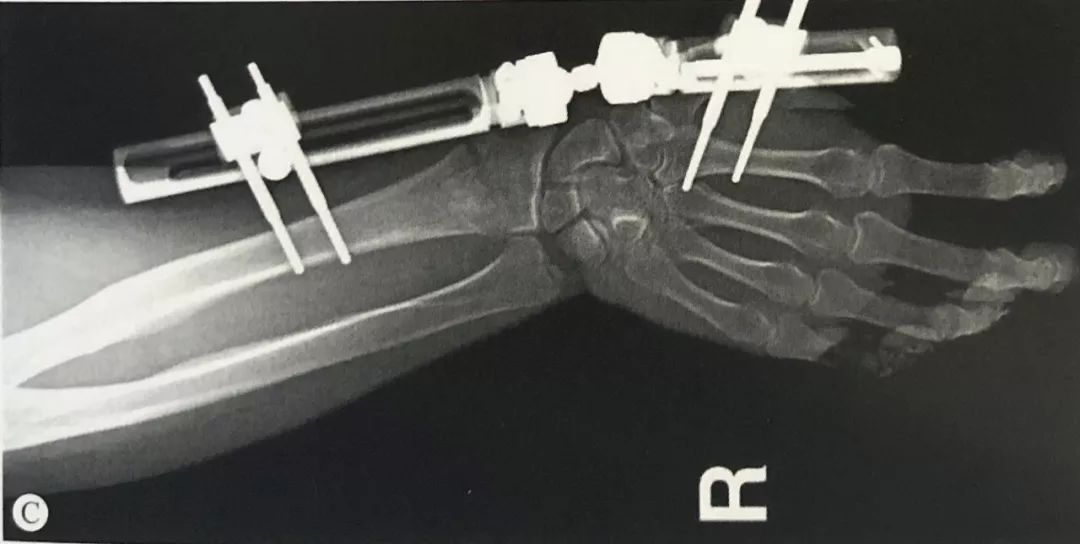

与掌骨螺钉在同一平面,套筒保护软组织导向器引导下置入2枚3mm Schanz螺钉。

手法牵引复位C形臂透视下检查骨折的复位情况。

维持复位的情况下,连接外固定支架,将外固定架旋转中心同腕关节旋转中心置于同一轴线上。

正侧位透视,检查桡骨长度、掌倾角和尺偏角是否恢复,调整固定角度直至骨折复位满意。